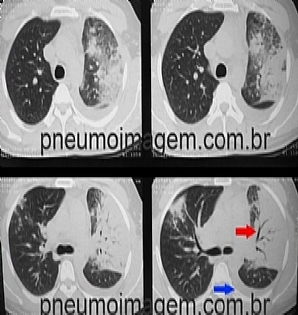

Veja imagens sobre pneumonia por S. pneumoniae no PneumoImagem,

clicando aqui.